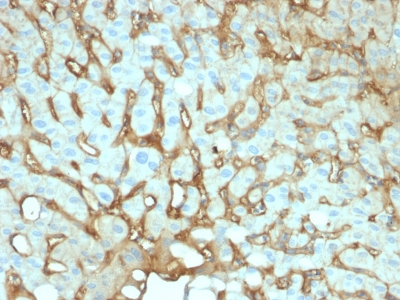

IHC (Immunohiostchemistry)

(Formalin-fixed, paraffin-embedded human Hepatocellular Carcinoma stained with Albumin Mouse Monoclonal Antibody (ALB/2144).)

IHC (Immunohistochemistry)